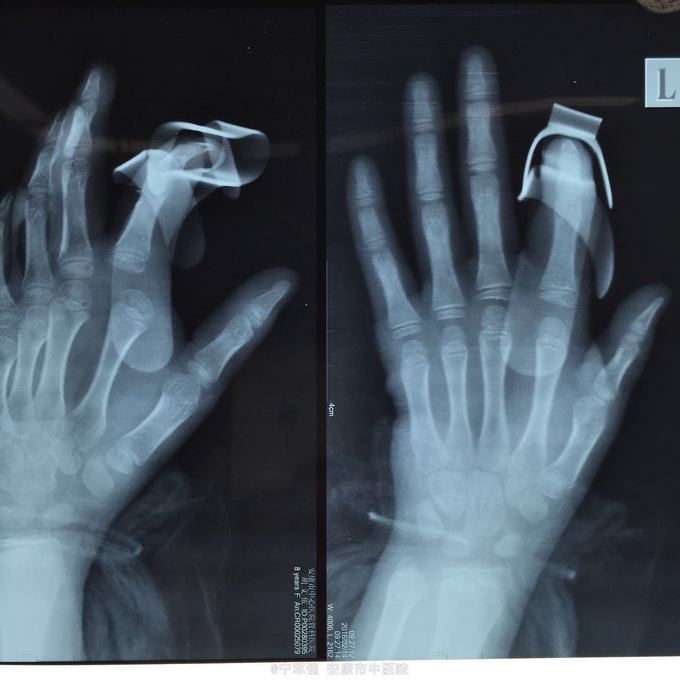

患者8岁,女 扭伤致左手食指肿痛活动受限2小时

患者一般情况良好,左手第二掌指关节处肿胀,弹性固定于伸直位,活动受限,压痛明显,循环尚可

诊断:左手第二掌指关节脱位 处理,予以手法复位失败!考虑关节囊坎顿,阻止复位 予以局麻小切口探查证实,复位脱位,修补关节囊

指骨夹板固定,复查x线显示复位良好 随诊